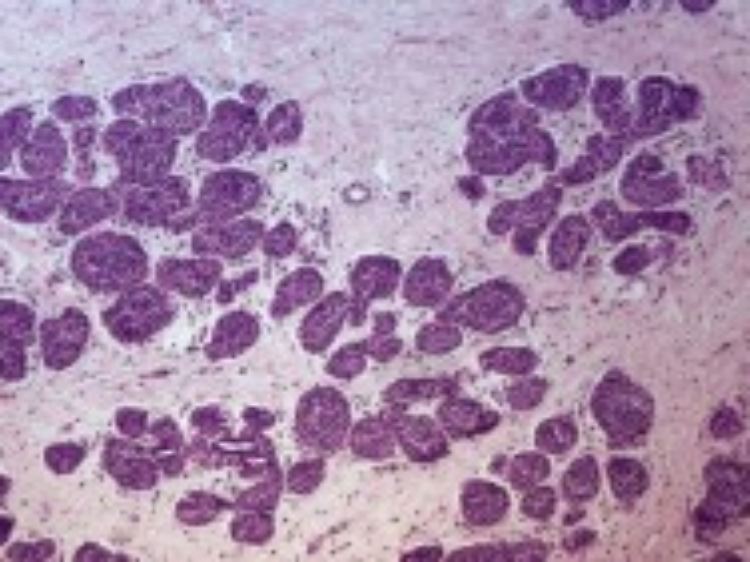

Der Brustkrebs ist in Deutschland der häufigste bösartige Tumor bei Frauen. Im Jahr 2010 rechnet das Berliner Robert Koch-Institut mit knapp 60.000 neuen Fällen. Mehr als 17.000 Frauen starben 2006 an dem Krebs. Jüngere Zahlen liegen nicht vor.